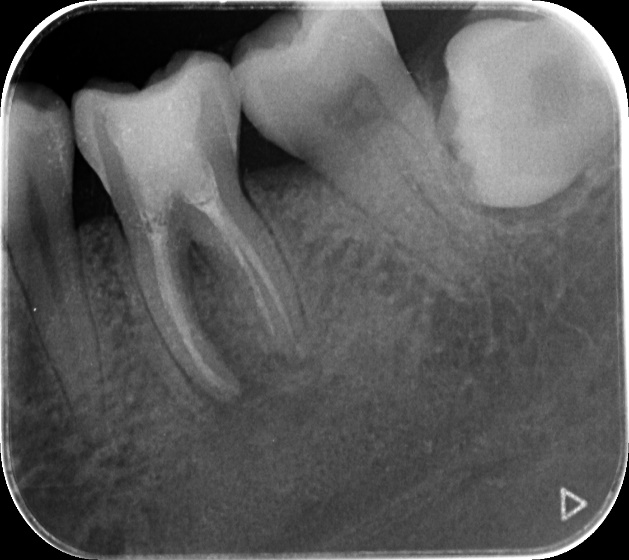

根尖片(小牙片)

根尖片用于检查单个牙齿的牙体、牙周及根尖周病变。根尖片投照技术有两种:分角线技术及平行技术。根管治疗过程中通常拍摄小牙片看牙胶尖放置是否到位,根管治疗后拍摄小牙片可观察牙胶尖是否充填到位。

根管充填完成后观察根管充填是否到位